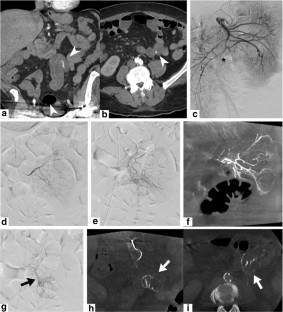

Fig. 1